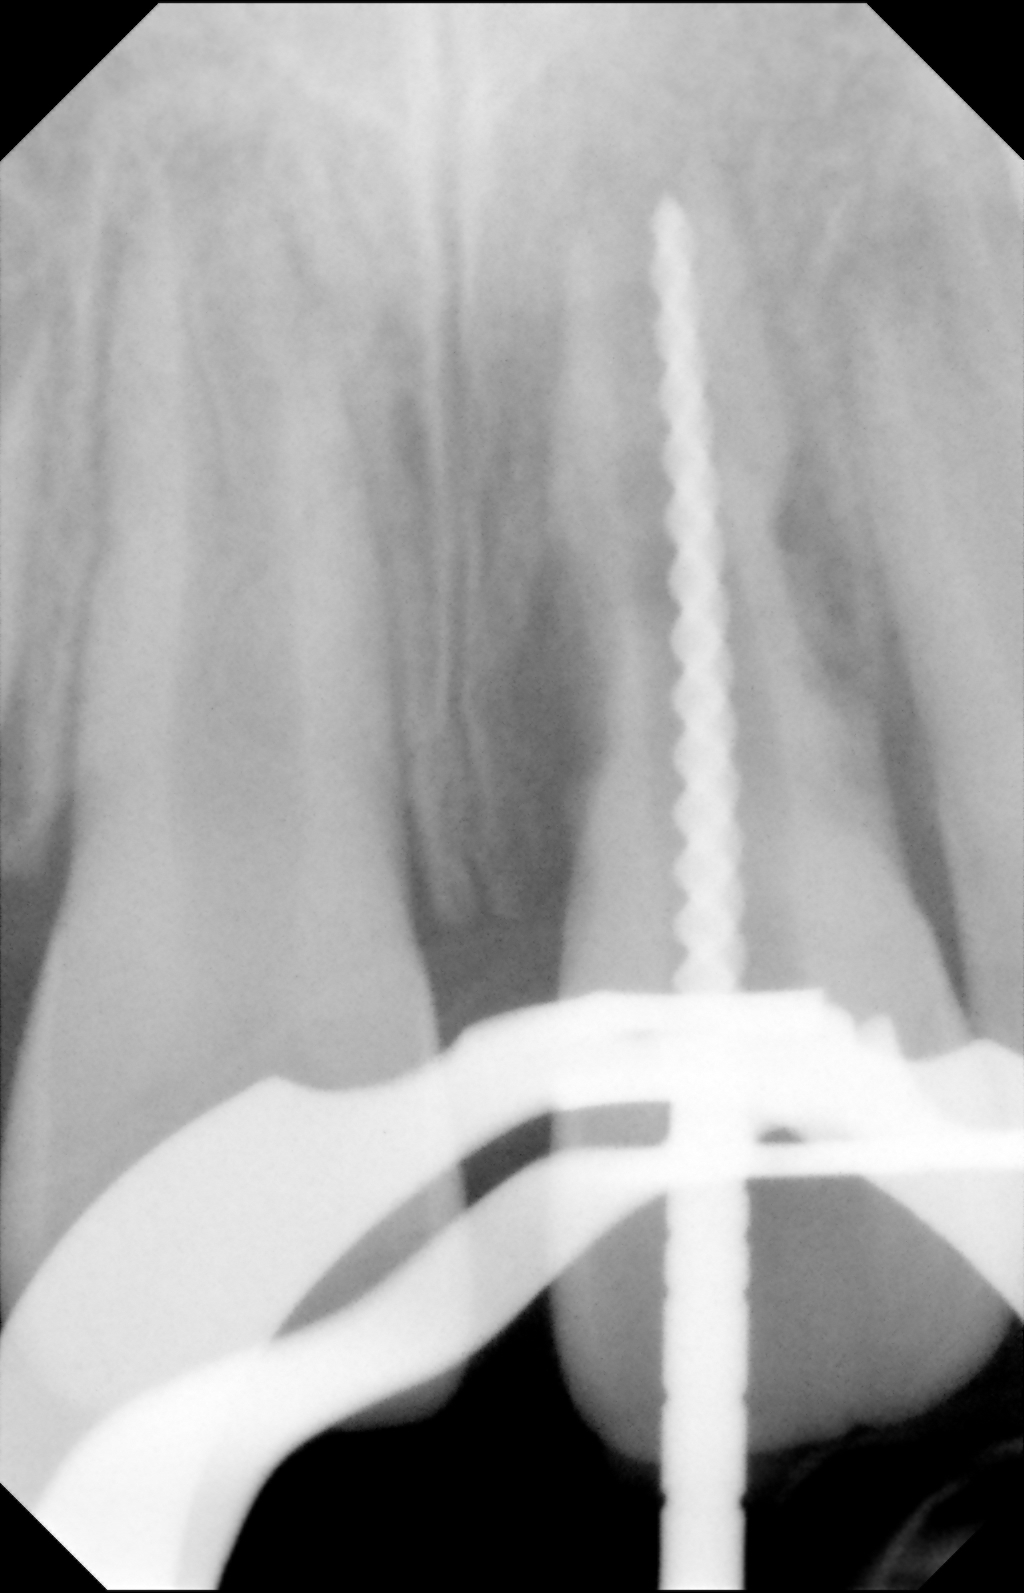

Clinical procedure: If apical bone loss is present (Figure 1) a collagen/gelatin sponge (eg, Gelfoam®, Pfizer Inc., www.pfizer.com) can be placed apically so that the MTA can be delivered to the desired working length. (Any other surgical resorbable sponge would also work, such as OraPlug® [Salvin Dental Specialties, www.salvin.com], Surgifoam® [Midwest Dental, www.mwdental.com], or Surgispon® [Aegis Lifesciences, www.surgispon.com]). This is done by taking a small piece (2 mm x 2 mm) of the resorbable sponge and pushing it down to and through the root apex with an endodontic file. Once this is done, MTA is packed down the canal with a custom-fitted cone. The clinician can use a rubber stopper on the gutta-percha cone to know the exact length of MTA placed in the apical third (Figure 2). Once the apical third is sealed with 3 mm to 5 mm of MTA, the remaining coronal canal space can be back-filled using a warm gutta-percha technique (Figure 3).

Fig 1. Preoperative radiograph showing apical bone loss.

Figure 1

Fig 2. MTA placed in the apical third.

Figure 2